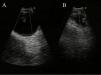

Varón de 65 años, fumador de 80 paquetes/año, que consultó por hemiparesia izquierda. En la tomografía axial computarizada (TAC) craneal se identificó una lesión ocupante de espacio parietal derecha indicativa de metástasis cerebral. La radiografía de tórax evidenció una masa pulmonar de bordes bien definidos en el lóbulo superior izquierdo (LSI). En la TAC toracoabdominal con contraste intravenoso se observó la masa pulmonar de 30×24mm en el LSI y adenopatías hiliares izquierdas de 32×18mm. Además, existía una imagen que morfológicamente podría corresponder a adenopatía paratraqueal superior derecha de 23×17mm, pero con densidad media de −7,9 unidades Hounsfield. En la broncoscopia no se observaron lesiones endobronquiales. Las citologías del broncoaspirado y el lavado broncoalveolar del LSI fueron negativas para malignidad. Mediante punción-aspiración transtorácica con aguja fina de la masa del LSI se obtuvo el diagnóstico citológico de adenocarcinoma. Se realizó EBUS-TBNA de la lesión paratraqueal superior derecha mediante ecobroncoscopio de sonda convexa (CP-EBUS) (modelo BF-UC160F; Olympus; Tokio, Japón), y se observó una lesión anecoica de 1,48cm que no presentó flujo con el modo Doppler. Tras la punción se obtuvieron 5cm3 de líquido amarillento y se comprobó la disminución de tamaño de la lesión (fig. 1). En el examen citológico del líquido se observó un frotis de fondo mixoide con células espumosas de hábito macrofágico compatible con quiste broncogénico.

El EBUS detecta fácilmente los quistes mediastínicos: los diferencia de las estructuras vasculares por la ausencia de flujo con el modo Doppler y permite, además, el diagnóstico citológico y el tratamiento mediante drenaje.